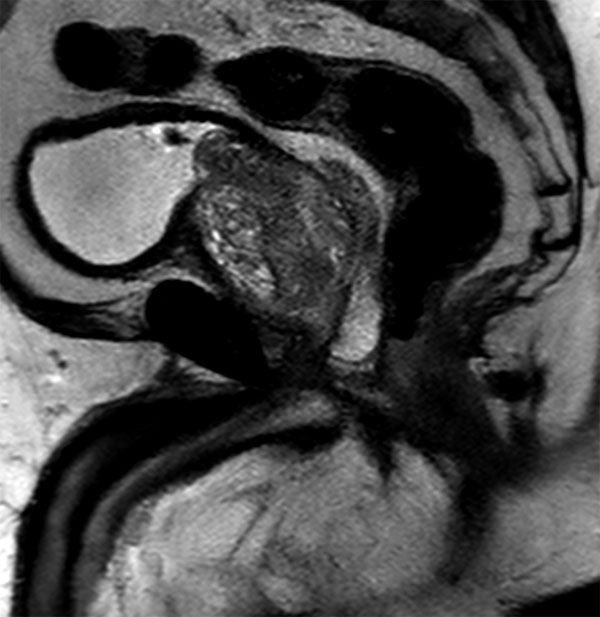

Sagittal SSh T2w TSE